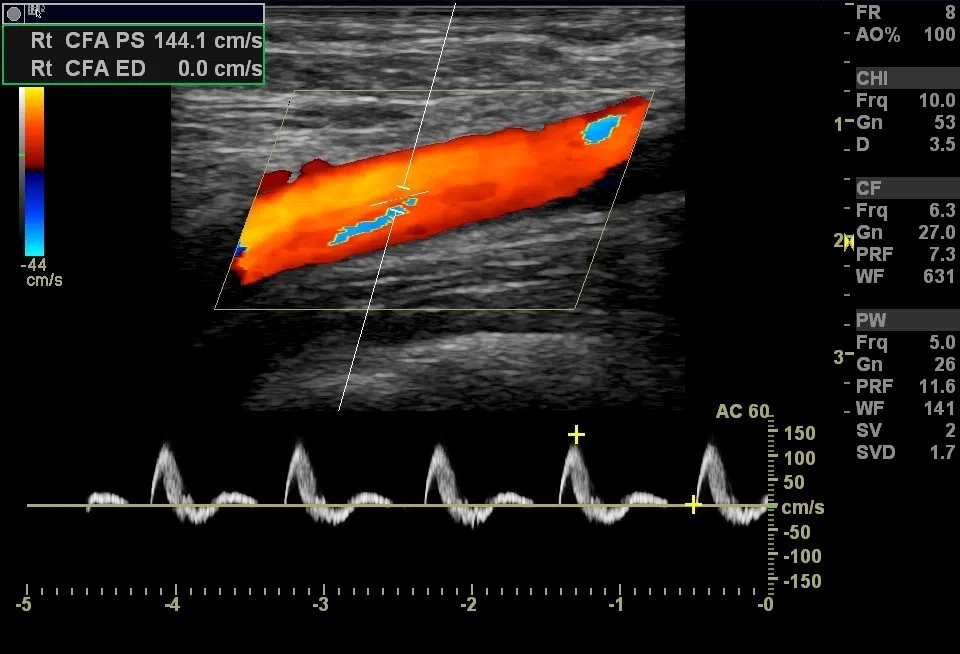

Siêu âm doppler cũng dựa trên cùng nguyên tắc, và nó có thể hoạt động có màu (doppler màu)hay không(doppler xung hay còn gọi là doppler liên tục).

Như vậy, siêu âm doppler cho phép phân tích tốc độ dòng máu trong động mạch

- Đo dòng máu bên trong động mạch;

- Tìm chỗ hẹp động mạch, kết hợp với tăng dòng máu trên doppler;

Yếu tố chính là tìm kiếm và phân tích tắc nghẽn động mạch bằng siêu âm doppler. Thật vậy, mức độ tắc nghẽn động mạch là một yếu tố rất quan trọng để thảo luận cách xử trí trong tương lai.